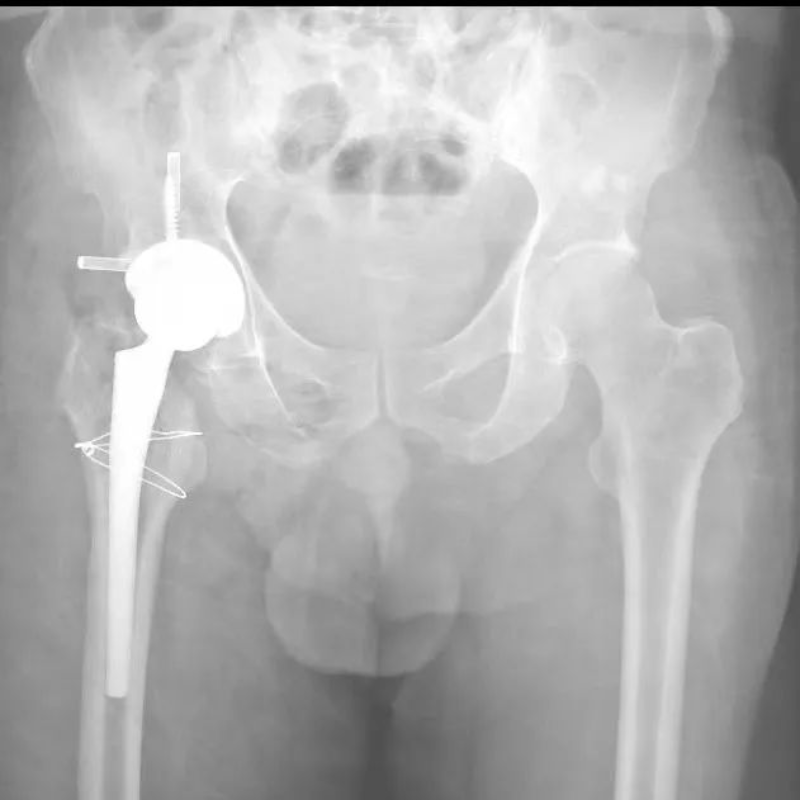

50多歲的朱大哥,20多年前因為車禍傷導(dǎo)致股骨頭缺血性壞死,一直一瘸一拐走路,就診時,右側(cè)髖關(guān)節(jié)股骨頭基本消失,髖臼磨損嚴(yán)重,關(guān)節(jié)已接近融合,肢體短縮有6-7cm,通過術(shù)前AI規(guī)劃,能精準(zhǔn)確定截骨的位置,髖臼杯安放的角度和尺寸等。手術(shù)進(jìn)展順利,術(shù)后關(guān)節(jié)功能恢復(fù)良好,肢體短縮明顯糾正無神經(jīng)損傷等并發(fā)癥,一個月后復(fù)查關(guān)節(jié)穩(wěn)定,患者從此告別一瘸一拐的日子。

文章配圖

△術(shù)前

△AI術(shù)前策劃

△術(shù)后